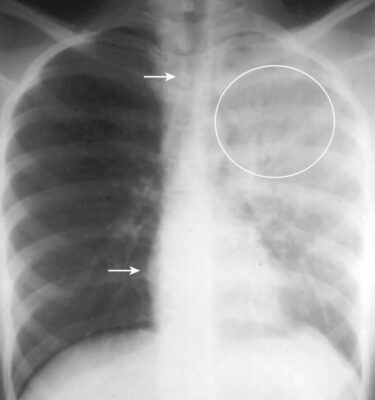

Tình huống: Anh S, 31 tuổi, đến khoa cấp cứu trong tình trạng khó thở cấp tính. Hình chụp X quang ngực thẳng của anh được thể hiện trong Hình 1.

- Như bạn có thể thấy, toàn bộ nửa phổi trái của anh S bị mờ.